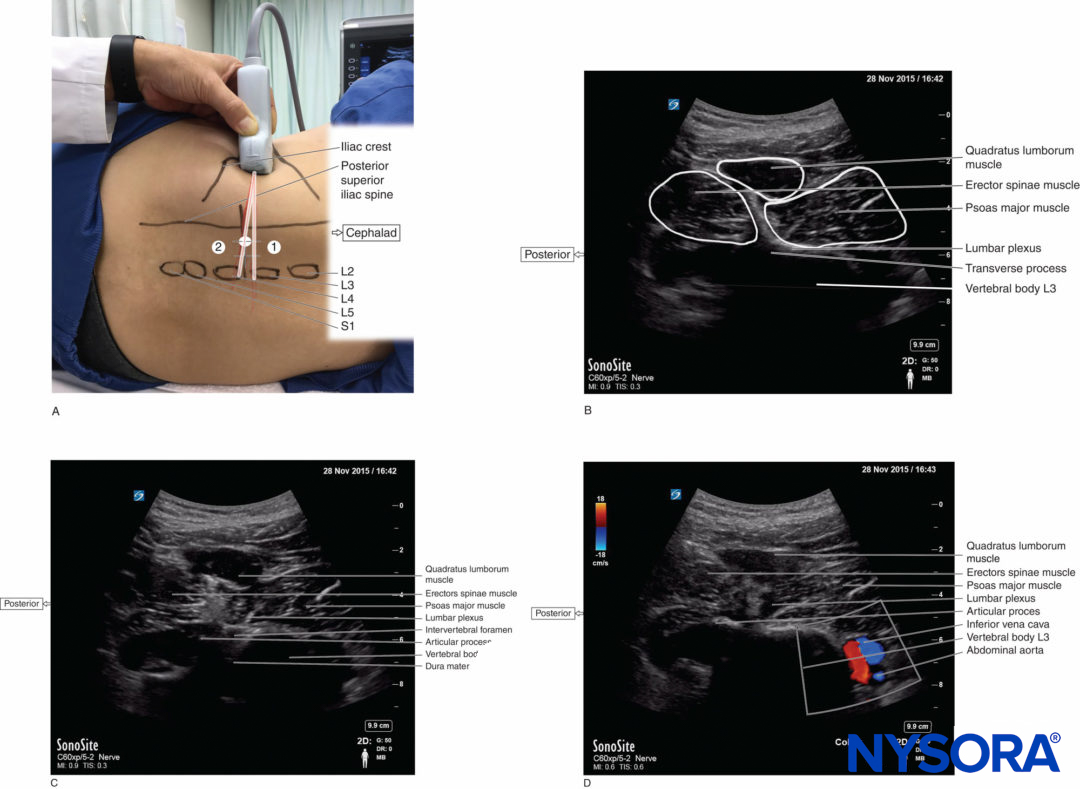

Recently, the “shamrock method” has become considered one of the standard approaches for US-guided LPB. In this method, the transducer is placed transversely in the abdominal flank adjacent to the iliac crest (Figure 3a). A shape like a shamrock with three leaves can be seen with the psoas major muscle anteriorly, the erector spinae muscle posteriorly, and the quadratus lumborum muscle at the apex of the transverse process (Figure 3b). The lumber plexus can be identified as a hyperechoic oval structure in the posteromedial compartment of the psoas major muscle near the transverse process. By tilting the transducer caudally, the L3 transverse process disappears from the US image, which permits an in-plane posteroanterior needle approach (Figure 3c). The needle insertion point is based on the landmark-guided method; that is, approximately 4 cm lateral to the midline or at the junction of the lateral third and medial two-thirds of a line between the spinous process of L4 and a line parallel to the spinal column passing through the posterior superior iliac spine. The needle insertion point can be decided by an ultrasonographical estimation of the distance from the bottom of the transducer to the posteromedial quadrant of the psoas major muscle, where the lumbar plexus is expected to locate. Then, the needle is advanced anteriorly under US guidance until the needle tip reaches to the lumbar plexus or an appropriate muscle twitch is observed. In this view, the inferior vena cava and abdominal aorta can be seen simultaneously anterior to the vertebral body (Figure 3d).

FIGURE 3. (A) Transducer position and needle insertion point to accomplish US-guided lumbar plexus block with the shamrock method using an in-plane approach. The transducer is placed transversely in the left side of the abdominal flank adjacent to the iliac crest to image the “shamrock” with the transverse process (1). By tilting the transducer (2), the transverse process disappears from the US image, which permits an in-plane posteroanterior needle approach. (B) US anatomy of the right lumbar paravertebral region at the level of the L3 transverse process in the shamrock view. A shape that looks like a shamrock with three leaves consists of the erector spinae, quadratus lumborum, and psoas major muscles and the transverse process. (Continued) (C) US anatomy of the right lumbar paravertebral region just caudal to the L3 transvers process (lumbar intertransverse space in the shamrock view). The lumbar plexus root is seen just lateral to the intervertebral foramen. The dura mater is confirmed as a hyperechoic line in the spinal canal through the intervertebral foramen. (D) The abdominal aorta and inferior vena cava are confirmed by color Doppler anterior to the vertebral body at the lumbar intertransverse space in the right-side shamrock view.

The shamrock method has been reported to have several advantages over US-guided LPB using paramedian transverse scan. First, the needle trajectory is almost the same as in the traditional landmark-guided LPB, which means that this method simply adds ultrasonographical information to the landmark-guided LPB approach. Second, needle can be advanced perpendicularly to the US beam, which allows for a clearer visualization of the needle.